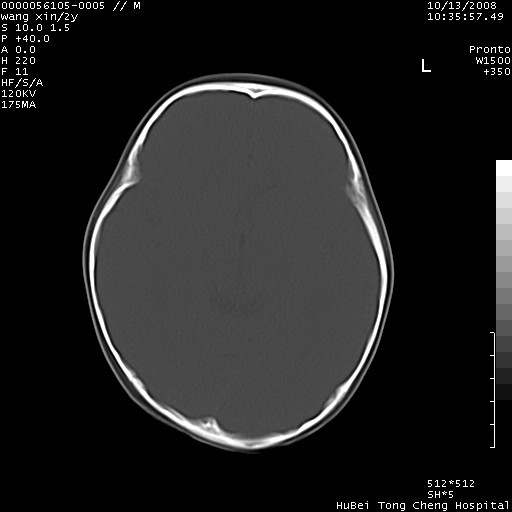

标题: PED1611:F,2Y。右侧额部小包块,光整,质硬,边界清楚,无 [打印本页]

标题: PED1611:F,2Y。右侧额部小包块,光整,质硬,边界清楚,无

右额骨内板压迫性变薄,呈椭圆形膨胀性骨吸收和低密度区,其间可见小斑片状致密影,-支持表皮样囊肿